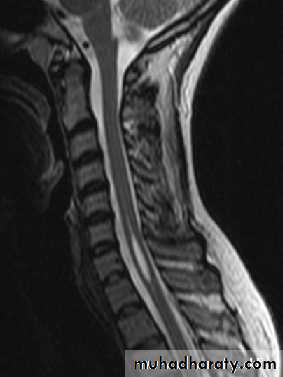

Syringomyelia

Cavitation of the spinal cord.The symptoms and physical signs reflect a pathology that starts centrally and expands outwards.

The cavity in syringomyelia affects crossing

spinothalamic fibers producing a half-cape or cape loss of pain and temperature sensation; posterior column signs are also found.